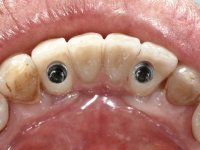

Após estudo imagiológico foi planificada a colocação de dois implantes de 3.3 mm de diâmetro e 10 mm de comprimento. No dia da cirurgia foram extraídos os dentes 42 e 32 e removido o implante. Os implantes foram colocados na zona dos alvéolos tendo o cuidado de lingualizar um pouco o seu posicionamento. Foi feita uma impressão pela técnica de moldeira aberta com o retalho aberto para a confeção da ponte provisória imediata. Enquanto a impressão foi para o laboratório, foram colocados parafusos de cicatrização altos e feita a sutura da ferida cirúrgica. A paciente esperou 2 horas na sala de espera enquanto no laboratório era confecionada a ponte provisória. A ponte provisória imediata aparafusada foi colocada e o seu assentamento controlado imagiologicmente. Passados 3 meses foi realizada a impressão definitiva com uma técnica de moldeira aberta. Nessa consulta aproveitamos para polir a ponte provisória com taças de borracha para que os tecidos moles pudessem maturar em melhores condições. Foi feita a recolha de informação para caracterizar da melhor forma a estrutura monolítica em Zr. Foram utilizadas guias de cor para a cerâmica de tonalidade coronária e gengival. No laboratório foi confecionada uma ponte em Zr. aparafusada que foi cuidadosamente caracterizada. Após aprovação pela paciente foi colocada definitivamente em boca. O aperto foi feito com uma chave dinâmica com 35 N de torque. Os orifícios foram tapados com teflon e obturados com resina composta.